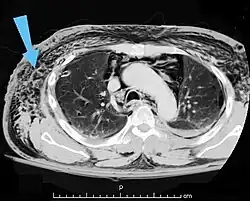

An abdominal CT scan of a patient with subcutaneous emphysema (arrows)